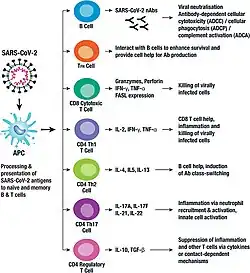

Although SARS-CoV-2 has a tropism for ACE2-expressing epithelial cells of the respiratory tract, people with severe COVID‑19 have symptoms of systemic hyperinflammation. Clinical laboratory findings of elevated IL‑2, IL‑6, IL‑7, as well as the following suggest an underlying immunopathology:[147]

- Granulocyte-macrophage colony-stimulating factor (GM‑CSF)

- Interferon gamma-induced protein 10 (IP‑10)

- Monocyte chemoattractant protein 1 (MCP1)

- Macrophage inflammatory protein 1‑alpha (MIP‑1‑alpha)

- Tumour necrosis factor (TNF‑α) indicative of cytokine release syndrome (CRS)

Interferon alpha plays a complex, Janus-faced role in the pathogenesis of COVID-19. Although it promotes the elimination of virus-infected cells, it also upregulates the expression of ACE-2, thereby facilitating the SARS-Cov2 virus to enter cells and to replicate.[157][158] A competition of negative feedback loops (via protective effects of interferon alpha) and positive feedback loops (via upregulation of ACE-2) is assumed to determine the fate of people with COVID-19.[159]

Additionally, people with COVID‑19 and acute respiratory distress syndrome (ARDS) have classical serum biomarkers of CRS, including elevated C-reactive protein (CRP), lactate dehydrogenase (LDH), D-dimer, and ferritin.[160]

Systemic inflammation results in vasodilation, allowing inflammatory lymphocytic and monocytic infiltration of the lung and the heart. In particular, pathogenic GM-CSF-secreting T cells were shown to correlate with the recruitment of inflammatory IL-6-secreting monocytes and severe lung pathology in people with COVID‑19.[161] Lymphocytic infiltrates have also been reported at autopsy.[129]

Among healthy adults not exposed to SARS-CoV-2, about 35% have CD4+ T cells that recognise the SARS-CoV-2 S protein (particularly the S2 subunit) and about 50% react to other proteins of the virus, suggesting cross-reactivity from previous common colds caused by other coronaviruses.[166]

Host cytokine response

The severity of the inflammation can be attributed to the severity of what is known as the cytokine storm.[168] Levels of interleukin 1B, interferon-gamma, interferon-inducible protein 10, and monocyte chemoattractant protein 1 were all associated with COVID‑19 disease severity. Treatment has been proposed to combat the cytokine storm as it remains to be one of the leading causes of morbidity and mortality in COVID‑19 disease.[169]

A cytokine storm is due to an acute hyperinflammatory response that is responsible for clinical illness in an array of diseases but in COVID‑19, it is related to worse prognosis and increased fatality. The storm causes acute respiratory distress syndrome, blood clotting events such as strokes, myocardial infarction, encephalitis, acute kidney injury, and vasculitis. The production of IL-1, IL-2, IL-6, TNF-alpha, and interferon-gamma, all crucial components of normal immune responses, inadvertently become the causes of a cytokine storm. The cells of the central nervous system, the microglia, neurons, and astrocytes, are also involved in the release of pro-inflammatory cytokines affecting the nervous system, and effects of cytokine storms toward the CNS are not uncommon.[170]

Immunity

The immune response by humans to SARS-CoV-2 virus occurs as a combination of the cell-mediated immunity and antibody production,[337] just as with most other infections.[338] B cells interact with T cells and begin dividing before selection into the plasma cell, partly on the basis of their affinity for antigen.[339] Since SARS-CoV-2 has been in the human population only since December 2019, it remains unknown if the immunity is long-lasting in people who recover from the disease.[340] The presence of neutralising antibodies in blood strongly correlates with protection from infection, but the level of neutralising antibody declines with time. Those with asymptomatic or mild disease had undetectable levels of neutralising antibody two months after infection. In another study, the level of neutralising antibodies fell four-fold one to four months after the onset of symptoms. However, the lack of antibodies in the blood does not mean antibodies will not be rapidly produced upon reexposure to SARS-CoV-2. Memory B cells specific for the spike and nucleocapsid proteins of SARS-CoV-2 last for at least six months after the appearance of symptoms.[340]